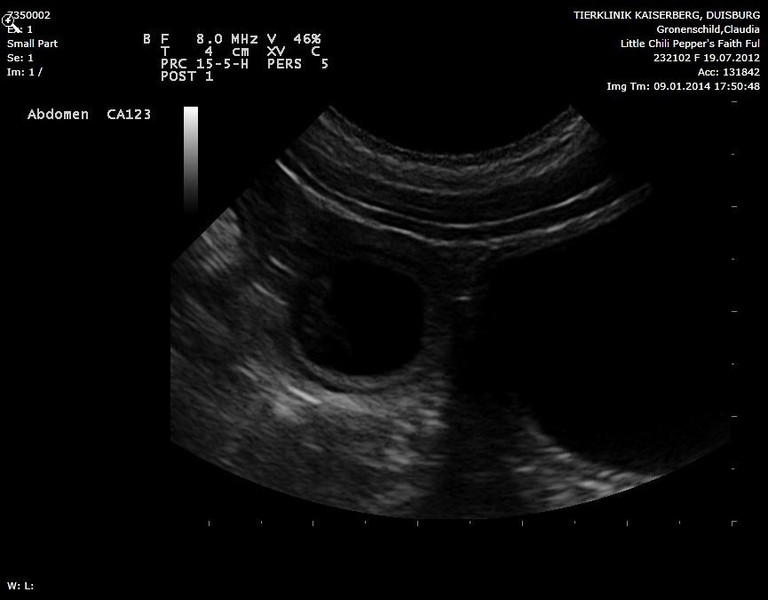

Ultraschallbilder vom 10.01.2014.